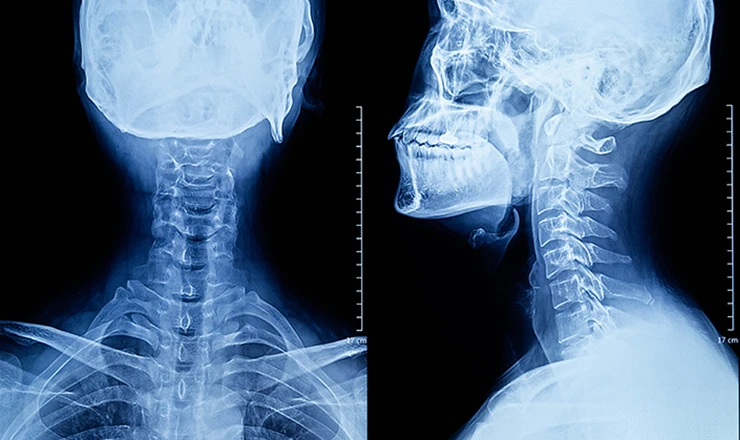

On-site X-Ray

Musculoskeletal